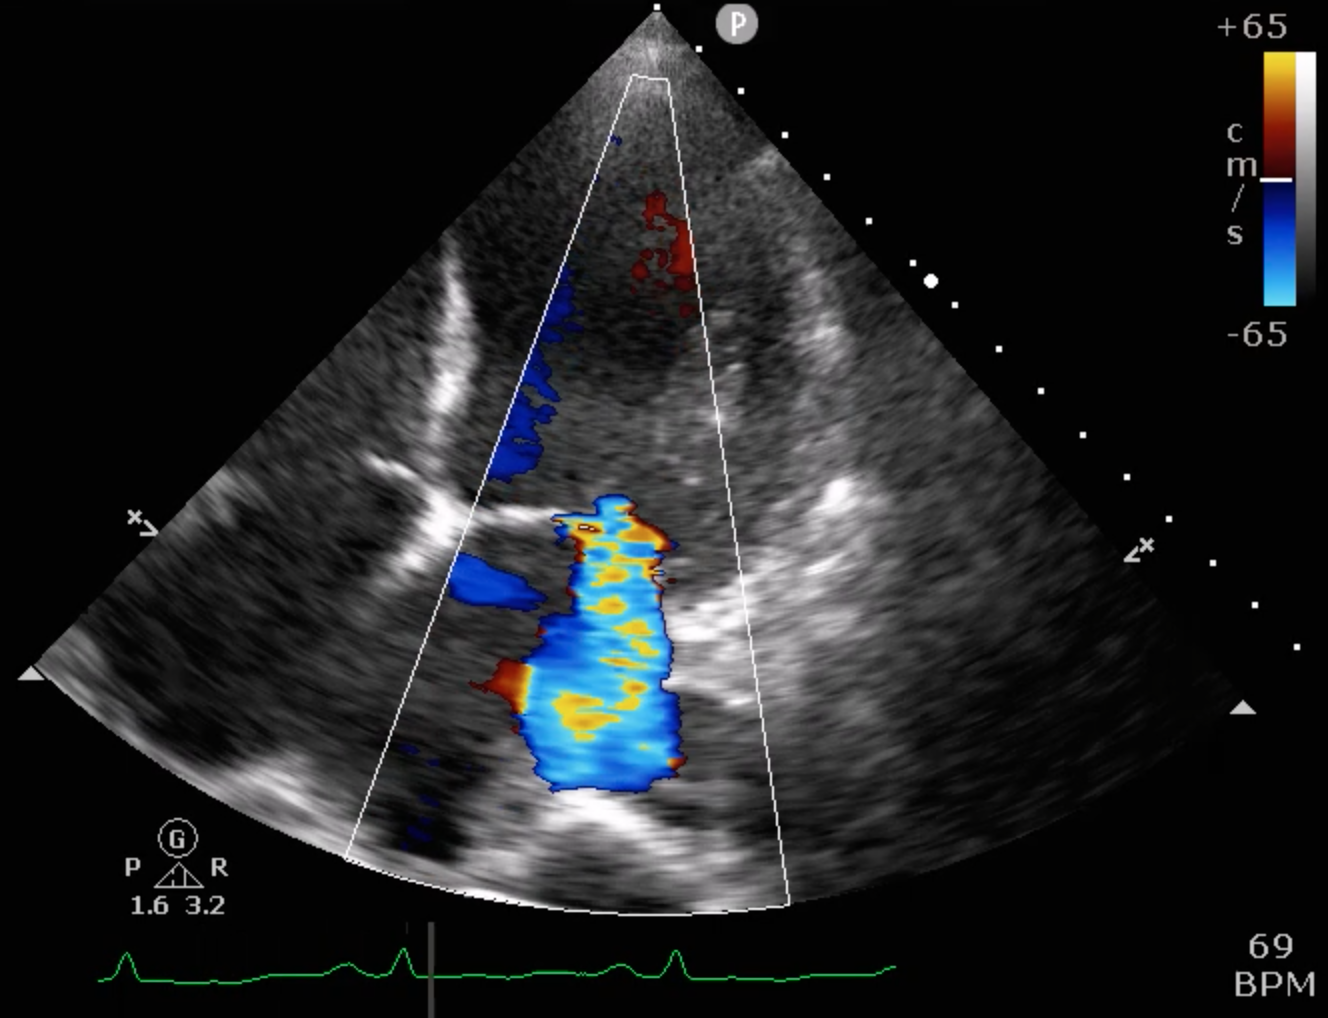

Relevant Test Results Prior to Catheterization

Echocardiography showed severely reduced LV systolic function with an EF around 20%, global hypokinesia, and anterior septal hypokinesia. Severe mitral regurgitation with left atrial enlargement was noted. Mild RV dysfunction was present, and Doppler suggested elevated filling pressures. These findings were obtained prior to catheterization.